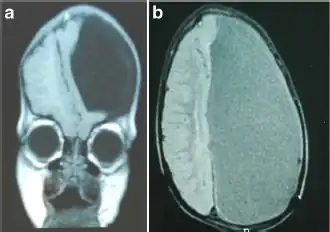

| a) MRI sagittal T1 scan demonstrating a left-sided hemihydranencephaly b) coronal | |

Hemihydranencephaly is a severe cephalic disorder characterized by complete or almost complete absence of the cerebral cortex with preservation of meninges, basal ganglia, pons, medulla, cerebellum, and falx. It is a special type of hydranencephaly.